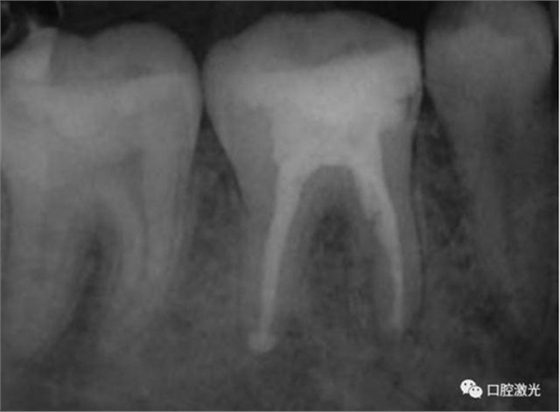

11、21 治療前

對瘺管位置進(jìn)行激光氣化

激光治療后即刻

治療前和2個月后效果對比